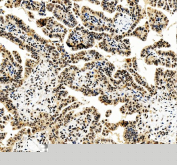

IHC staining of FFPE human lung cancer tissue with FOXL2 antibody, HRP-secondary and DAB substrate. HIER: boil tissue sections in pH8 EDTA for 20 min and allow to cool before testing.